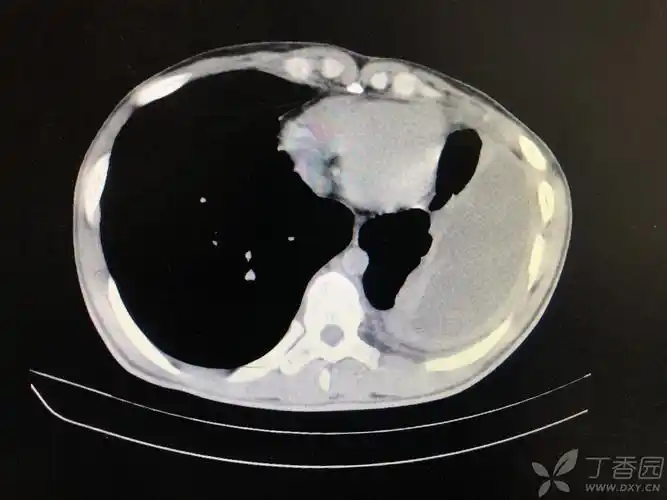

胸腔积液 [病例帖]